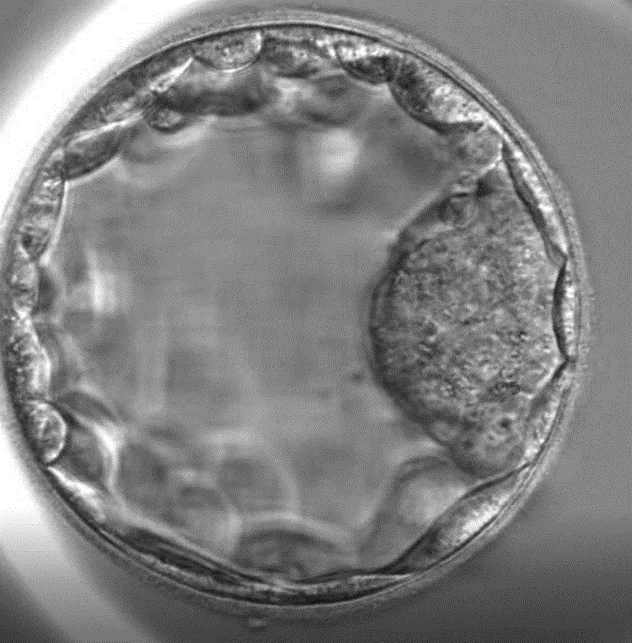

Quinto giorno: Blastocisti

Il quinto giorno si forma la blastocisti. Le cellule sono formate dall’embrioblasto interno, da cui si sviluppa successivamente il feto e il trofoblasto esterno, da cui si forma la placenta.

In questa fase, gli embrioni vengono trasferiti in utero o conservati mediante vitrificazione per un ulteriore utilizzo.

Embrione allo stadio di blastocisti. Trofoblasto ed embrioblasto possono essere distinguibili.